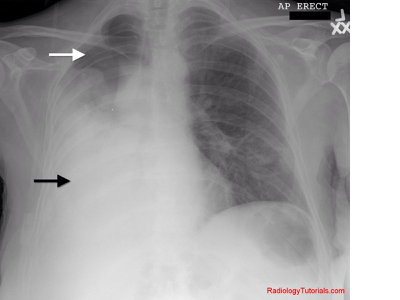

A collection of blood in the space between the chest wall and the lung (the pleural cavity)

Definition